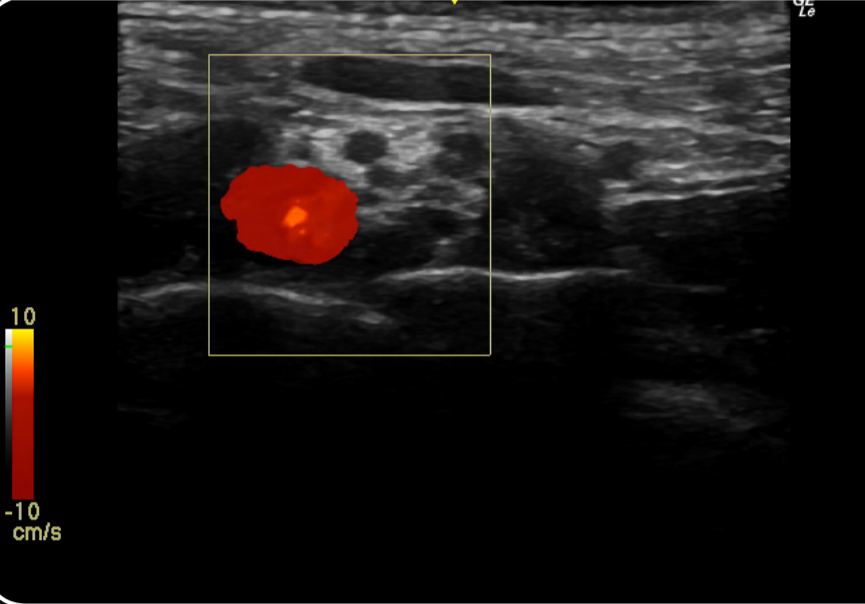

- Sonda con apuntador, para optimizar el trabajo de anestesiólogos.

- Innovador software específico para anestesia y transductores que ayudan a ver la aguja de anestesia.

- Usos de dos tipos de ultrasonido, uno para detectar metal, otro para tejido.